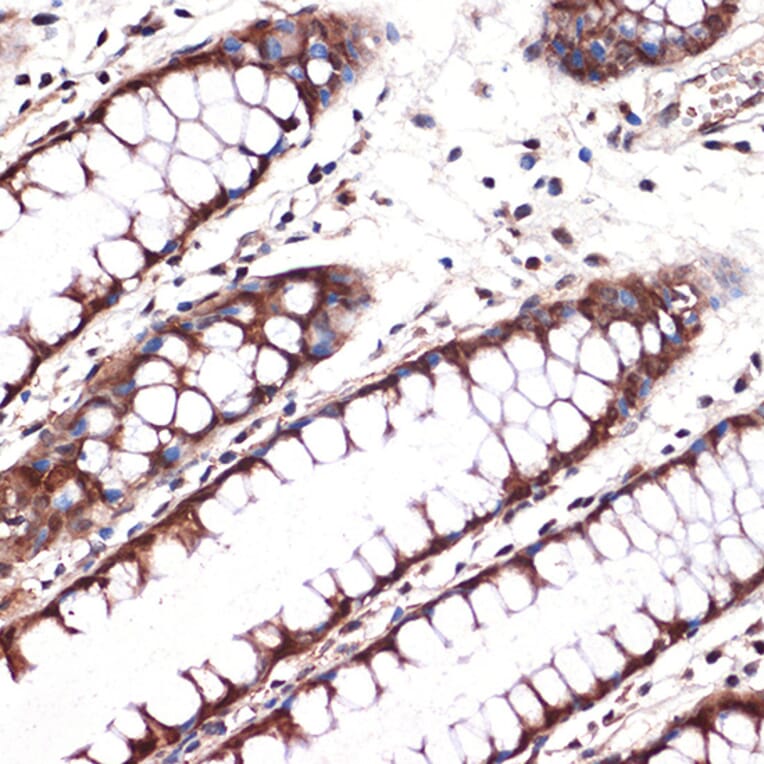

Immunohistochemistry analysis of paraffin-embedded human colon tissue using Anti-Carbonic anhydrase 2/CA2 Antibody [ARC1451] (A305662) at a dilution of 1:100 (40x lens). Perform microwave antigen retrieval with 10 mM Tris/EDTA buffer pH 9.0 before commencing with IHC staining protocol.